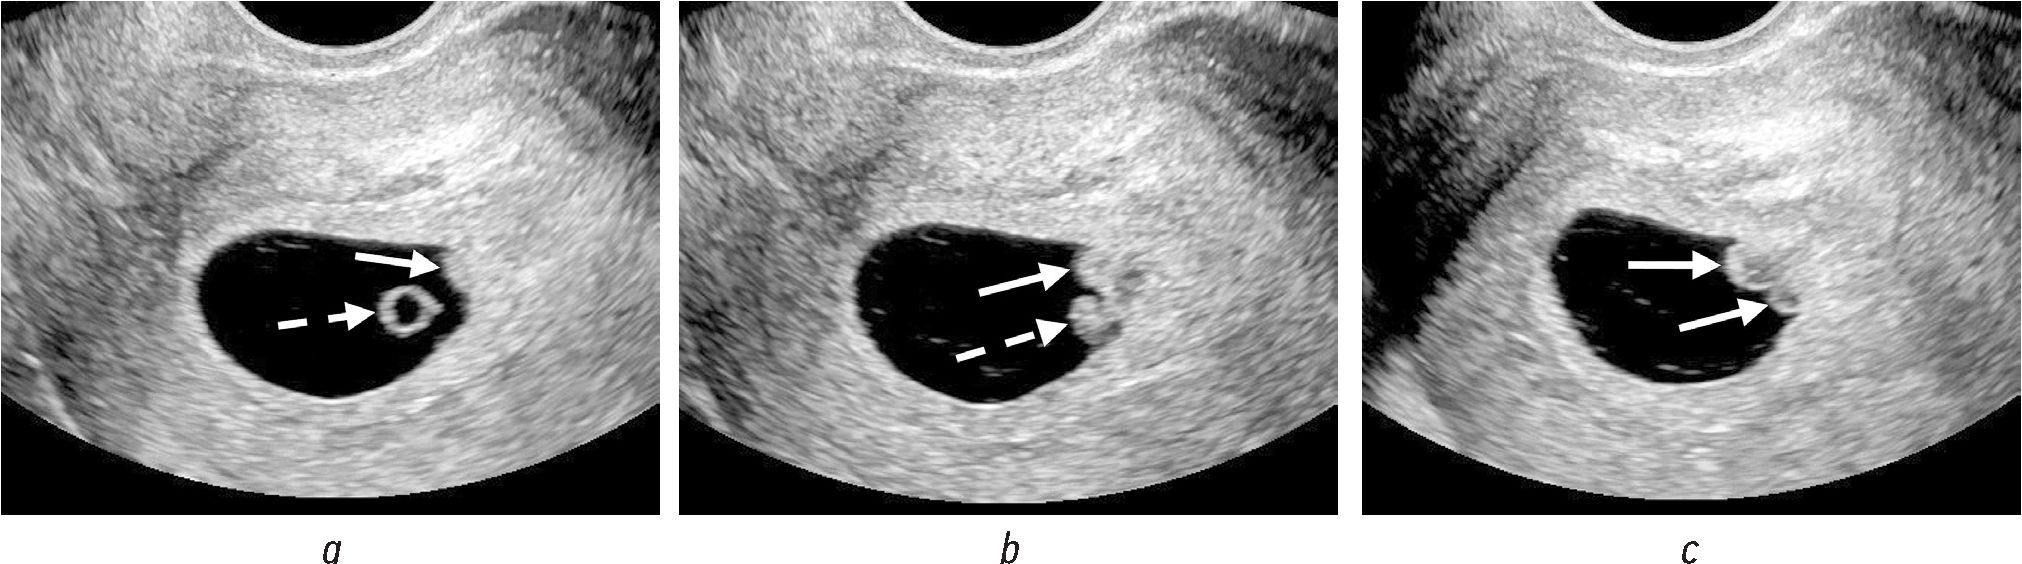

Наиболее частые и характерные сонографические признаки ХВ (рис. 1, а, b; рис. 2, а–c) [1, 2, 4, 6, 10–12]:

Рис. 2. На последовательных трансвагинальных сонограммах визуализируются желточный мешок (а, пунктирная стрелка), эмбрион (b, пунктирная стрелка), два ХВ частично (a и b, сплошные стрелки) и полностью (c, сплошные стрелки), гипоэхогенные в центральной части с периферическим гиперэхогенным ободком

1) выпячивание хориона в полость плодного яйца в первом триместре;

2) выпячивание локализуется в месте прикрепления пуповины к хориону или в непосредственной близости;

3) форма выпячивания овоидная или полипоподобная;

4) выпячивание чаще образует острые углы с поверхностью хориона;

5) выпячивание имеет разную эхоструктуру и эхогенность: солидную или жидкостную, от гипоэхогенных до гиперэхогенных, часто в виде центральной гипоэхогенной области с периферическим гиперэхогенным ободком;

6) хориальное выпячивание бессосудистое при цветовом и/или энергетическом допплеровском картировании;

7) в режиме реального времени в выпячивании визуализируется завихрение эхосигналов;

8) чаще одиночное, реже множественное.